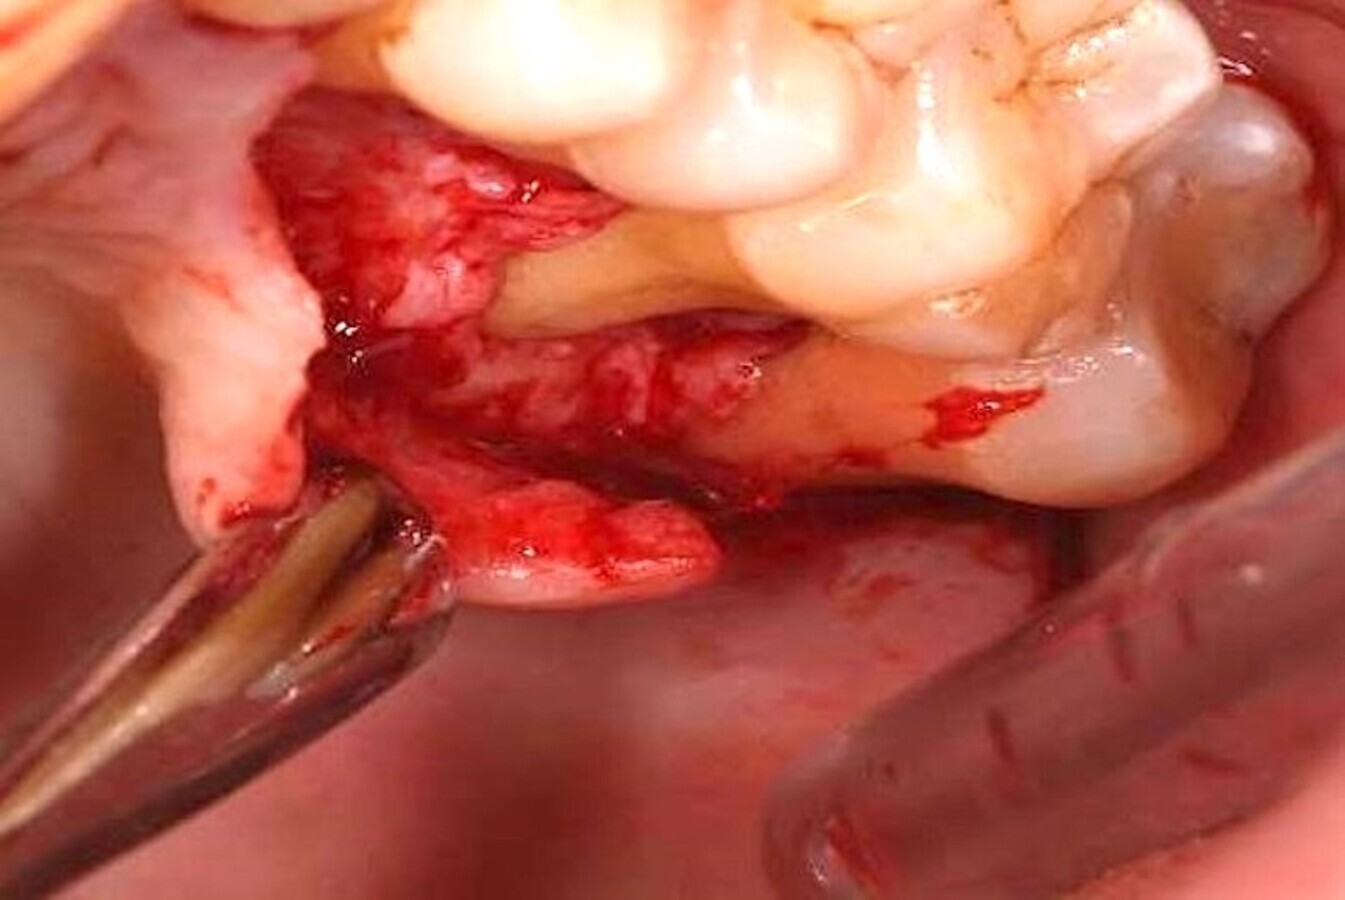

Algunos láseres como los de erbio, y en mi día a día en concreto el de Er,Cr:YSGG (Waterlase), permiten realizar un corte óseo quirúrgico muy preciso (Figuras 9-13), que transmite un daño térmico mínimo a los tejidos adyacentes9.

El láser Er,Cr:YSGG de alta potencia permite realizar cortes óseos quirúrgicos muy precisos (ver Figuras 9-13).

Figura 9.

Figura 10.

Figura 11.

Figura 12.

Figura 13. Las figuras 9-13 permiten observar un corte óseo quirúrgico muy preciso realizado con láser de erbio que produce un daño térmico mínimo en los tejidos adyacentes.